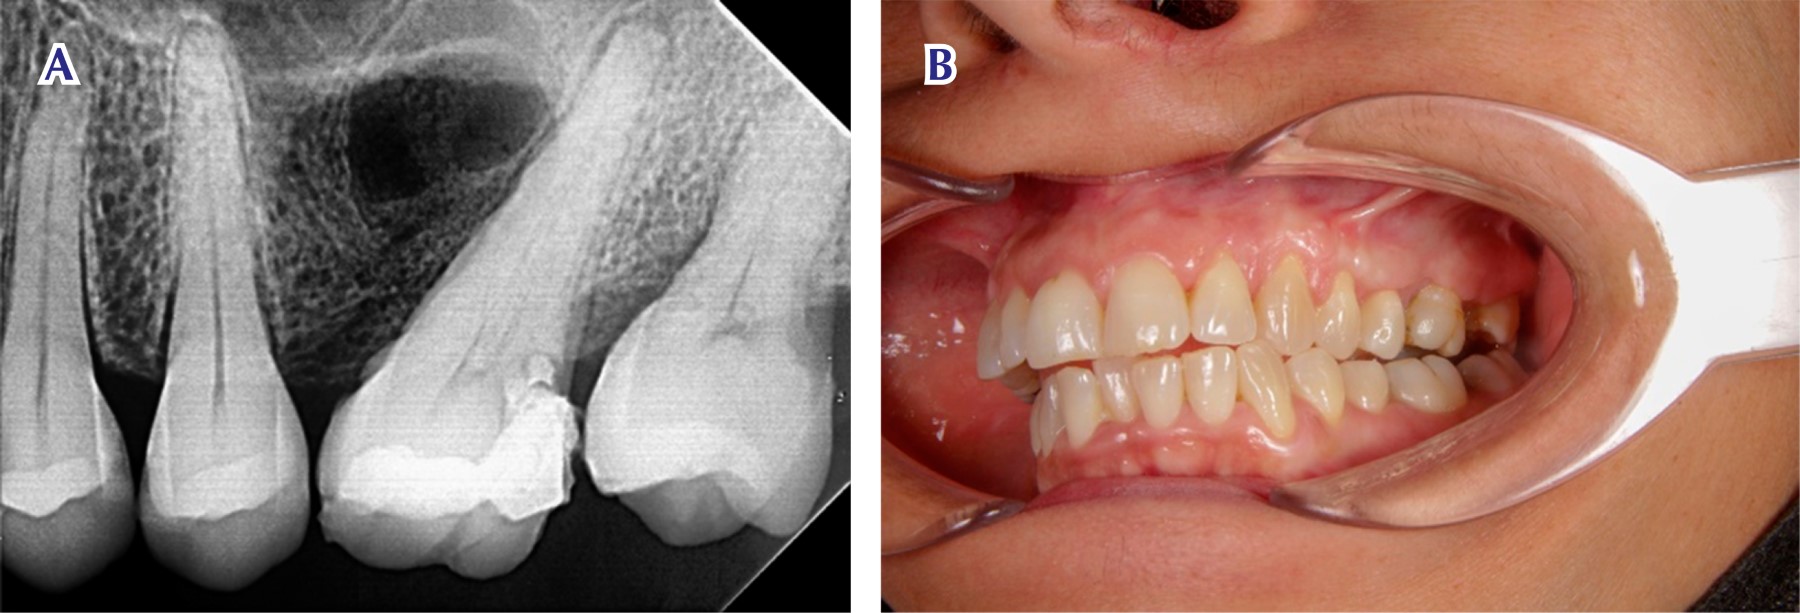

Figure 3